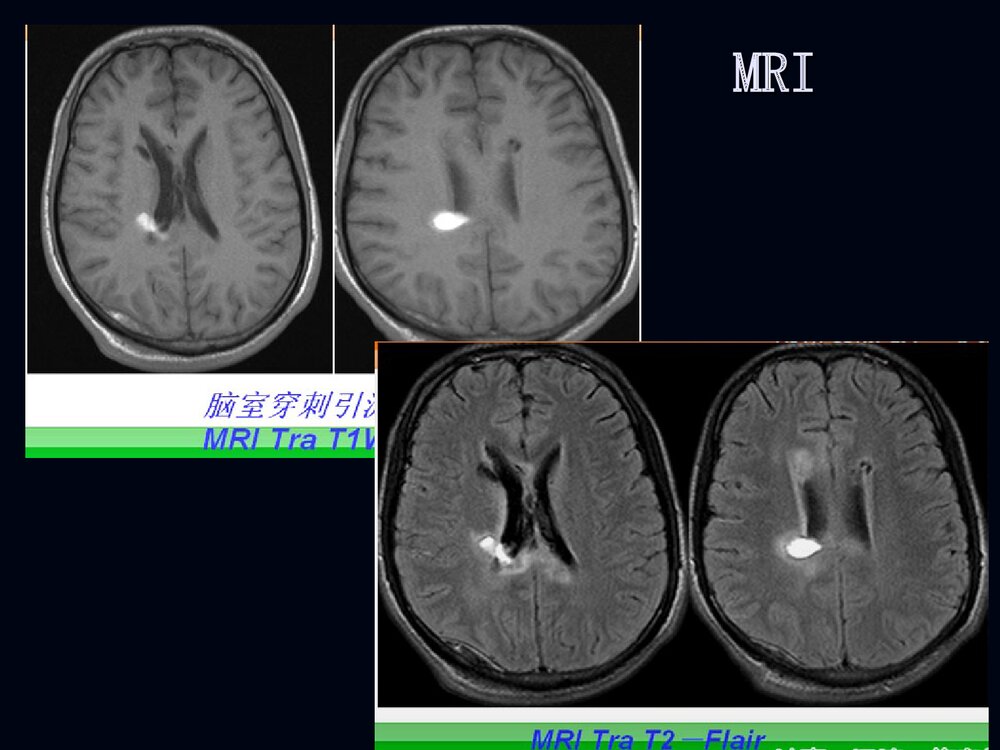

1烟雾病临床和影像诊断烟雾病临床和影像诊断2男性,男性,2020岁突发剧烈头痛岁突发剧烈头痛11小小时时3脑室穿刺脑室穿刺引流后增引流后增强强CTCT4MRIMRI5MRAMRA67病例病例22F、38Y,右侧肢体无力伴言语不清24天8MRIMRI910病例1DSA11烟雾病烟雾病病例2脑底异常血管网1213烟雾病烟雾病概述概述病理病理分型、分期分型、分期临床表现临床表现影像表现影像表现诊断诊断鉴别诊断鉴别诊断治疗治疗14概述概述烟雾病是以颈内动脉虹吸部或大脑前、中烟雾病是以颈内动脉虹吸部或大脑前、中动脉起始部缓慢的进行性的自发性狭窄或闭塞、动脉起始部缓慢的进行性的自发性狭窄或闭塞、并在脑底出现异常的小血管网为特点的一种脑血并在脑底出现异常的小血管网为特点的一种脑血管病。管病。在脑血管造影时,脑底...